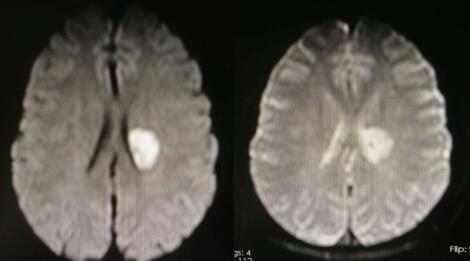

三、影像资料

MR颅脑平扫(1.5T)检查所见:左侧基底节-放射冠区示斑片状稍长TI稍长T2信号影,FLAIR序列呈稍高信号,双侧大脑半球皮层下白质内示少许斑点状等T1长T2异常信号影,FLAIR序列呈高信号,脑室系统未见扩张,脑沟、脑裂及脑池未见增宽,中线结构居中。矢状位示小脑、脑干及垂体未见异常。鼻咽顶后壁软组织稍增厚。右侧上颌窦黏膜稍增厚,余各鼻旁窦腔清亮。

四、临床诊断:左侧大脑基底节-放射冠区脑梗死